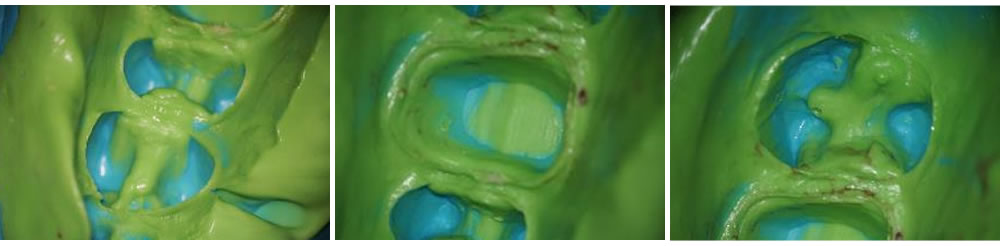

歯の形を整えたら、歯型を取ります。ゴム性の材料で型取りし、細部まできちんと歯形が取れているか確認します。

(左)噛む面から見たところ(中)横から見たところ(右)参考のための他の歯(前歯)